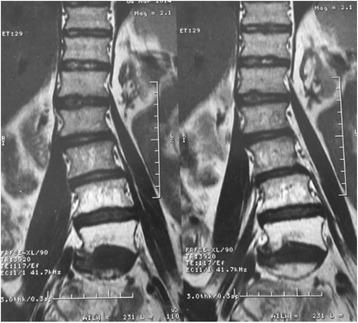

Radiation induced Lumbosacral plexophaty (RILP) is a rare but severe complication that has a considerable impact on quality of life. Its occurrence is rare but increasing with improved long-term cancer survival. This entity commonly results in different degrees of sensory and motor deficits. The pathophysiological mechanisms are not yet fully understood. Diagnosis of radiation myelopathy in women with gynecologic malignancies may increase with the use of concomitant chemo-radiation. This report describes the effect of this combination therapy in a 64-year-old woman with cervical carcinoma.

放射性腰骶丛神经病(RILP)是一种罕见但严重的并发症,对生活质量有相当大的影响。其发生率虽低,但随着癌症患者长期生存率的提高而呈上升趋势。该病症通常会导致不同程度的感觉和运动功能障碍。其病理生理机制尚未完全明确。随着同步放化疗的应用,妇科恶性肿瘤女性患者放射性脊髓病的诊断可能会增加。本报告描述了这种联合治疗对一名64岁宫颈癌女性患者的疗效。